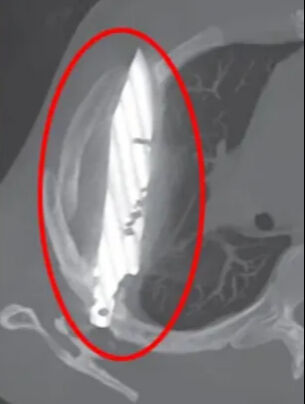

Röntgende adamın göğsünde saplı duran bir bıçak olduğu görüldü. Bunun üzerine açıklamalarda bulunan hasta, yaklaşık 8 yıl önce karıştığı bir kavga sırasında yüzünden, sırtından, göğsünden ve karnından yaralandığını, o zaman tedavi gördüğünü, ancak bıçağın saplandığını fark etmediklerini söyledi. O günden bu yana ciddi bir sağlık sorunu yaşamadığını söyleyen adam, gördükleri karşısında şaşkına döndü.

The Sun’ın haberine göre, sağ kürek kemiğinden girip hayati organlara zarar vermeden göğüste saplı kalan bıçak, acil ameliyatla alındı.